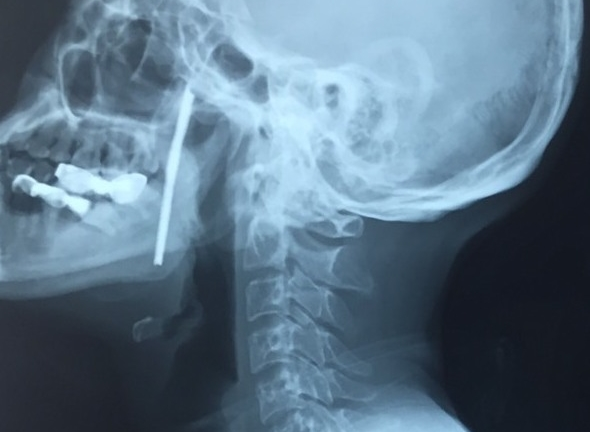

Cứu người đàn ông bị thanh sắt đâm xuyên cổ

Bệnh viện Hữu nghị Việt Đức vừa cấp cứu thành công trường hợp anh L.V.T (40 tuổi, trú tại Sơn La) bị tan nạn lao động.